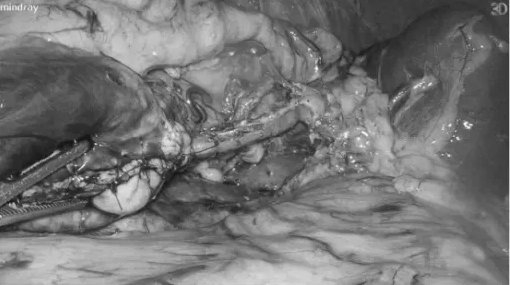

为了实现保脾、保功能的目标,手术中的每一次分离都轻柔精准,小心翼翼地推开脆弱的脾动静脉血管;每一步切除都稳准把控,仅切除病变胰尾及肿瘤,最大限度保留正常胰腺组织。全程视野清晰、操作稳准,细致到每一根血管、每一层组织,如同在“刀尖上跳舞”。

最终,陈艳军主任团队以极致细致、极致轻柔、极致保功能的手术态度,圆满完成了腹腔镜保脾胰体尾切除术(Kimura术式)。术中出血仅40ml,不仅完整切除肿瘤,更完美保留了脾脏及其血供、保留了大部分胰腺功能,实现了真正意义上的保器官、保功能、保未来。